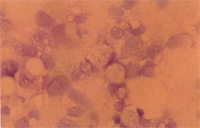

溶氧:6.50ppm,pH:7.0,透明度:13cm,懸浮固形物:190ppm,總氨一氮濃度:0.03ppm,亞硝酸一氨濃度:0.21ppm。2. 細菌檢驗: (1) 臟器(脾臟、腎臟等)塗抹片經革蘭氏染色鏡檢見到G(+)球菌。 (2) 自臟器 (腎臟、脾臟、肝臟等)釣菌在 BHI培養,經API20NE鑑定為:Streptococcus sp.和Aeromonas hydrophila。 3. 臟器塗抹檢驗:

脾臟、腎臟塗抹片以快速染色法(Diff-Quick)染色鏡檢,可在吞噬細胞的細胞質中見到多量藍色顆粒,細胞核則被擠到一邊,疑似類立克次體。4. 電子顯微鏡檢驗: